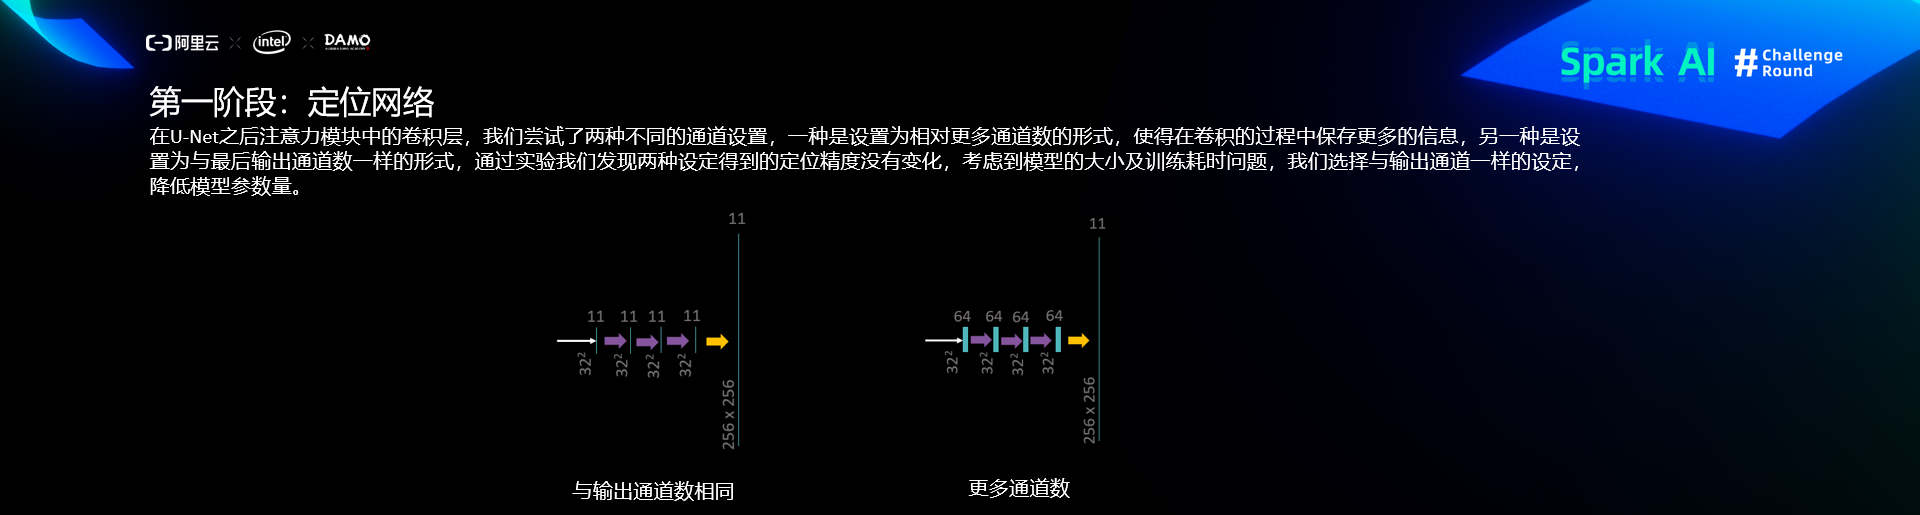

定位网络